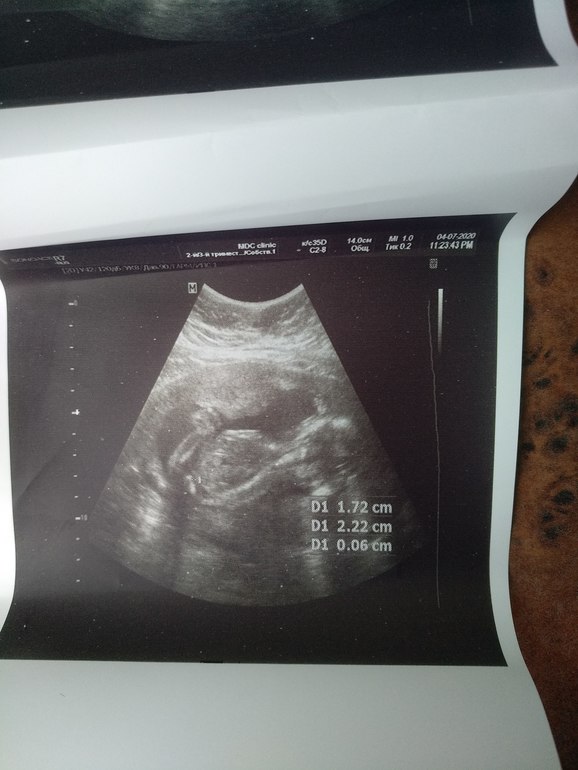

На 2 и 3 фото точно мальчика разглядела!

Врачь сказала мальчик , но я что то ни одного фото не увидела где точно мальчик , и не верится мне , мне кажется она ошиблась , результат НИИП уже жду месяц, мой гинеколог ушла в отпуск , вот скоро второй скрининг еще там спрошу, просто хотела что б вы все посмотрели, не одна я ничего не вижу , хотя доктор говорит я вам везде плюсики поставлю где смотреть , ну что то беленькое и все , вот что я вижу.

Где плюсик стоит, там видно «кофейное зернышко» -это на девочку указывает... мне вот на втором скрининге Доктор сказал «девочка», хотя я нипт делала, и уже в 11 недель знала, что будет здоровый мальчик))) Желаю вам мальчика, А главное ,пусть пусть будет здоровый малыш!!!